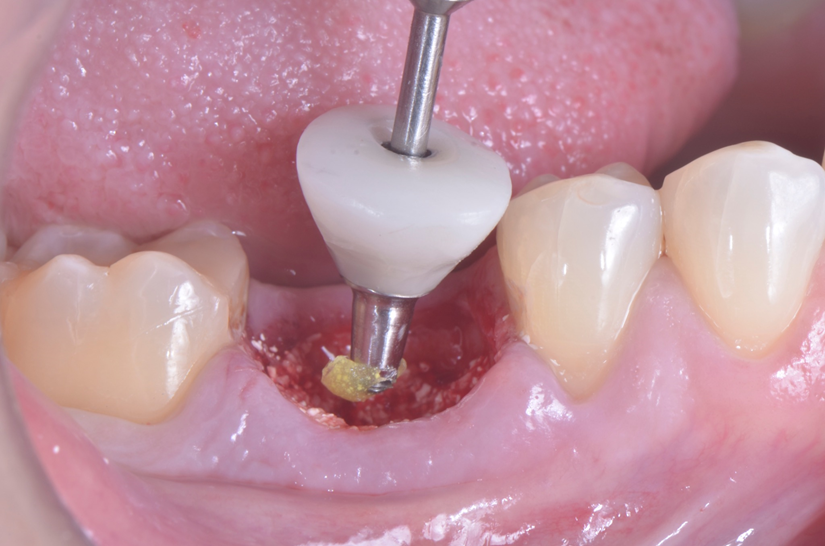

O paciente apresentou fratura vertical mésio-distal no elemento 46. Foi planejada a exodontia minimamente traumática e instalação imediata do implante Maestro Superiore (Implacil Osstem) utilizando uma guia prototipada. Após a exodontia, o implante foi instalado seguindo o protocolo de cirurgia guiada. O GAP vestibular foi preenchido com o Extra Graft. Um cicatrizador personalizado impresso com haletas facilitadoras foi capturado com resina flow e instalado. Após 30 dias, foi realizado escaneamento indireto para obtenção do perfil de emergência, utilizando protocolo digital com sobreposição do cicatrizador escaneado para confecção da coroa definitiva em zircônia policristalina estabilizada por ítria.

O uso de cicatrizadores personalizados, especialmente confeccionados por impressão 3D, tem ganhado destaque por permitir a conformação tecidual progressiva, facilitando a reprodução do perfil de emergência no fluxo digital6,7. A captura do cicatrizador com haletas de retenção com resina flow e seu posterior escaneamento são etapas críticas para assegurar a fidelidade da transferência do perfil de emergência e garantir um planejamento restaurador mais previsível8.

Neste caso, a sobreposição digital entre o cicatrizador escaneado e o desenho da coroa possibilitou comparar perfis de emergência com excelente adaptação clínica, contribuindo para um resultado estético e funcional adequado.